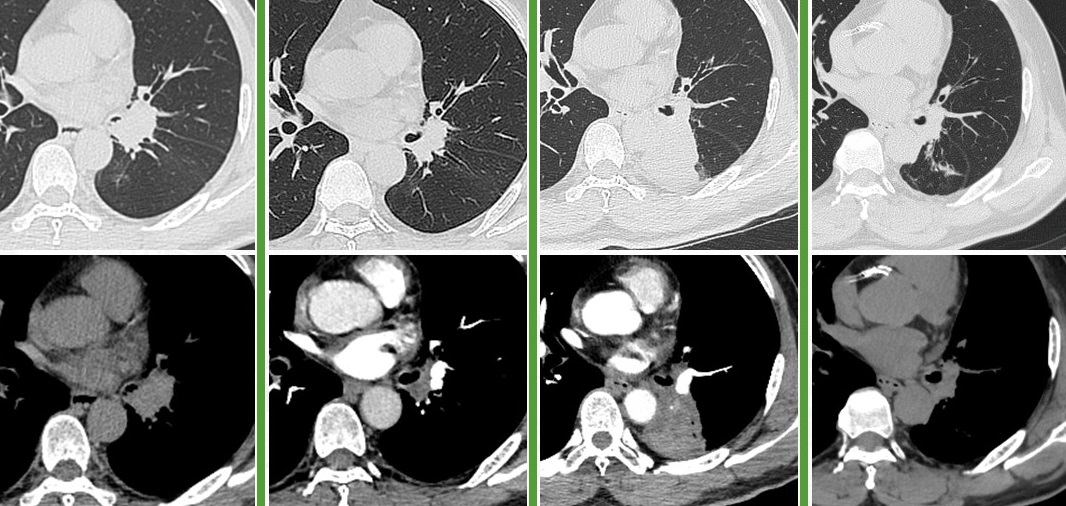

图:左起依次为三线治疗前、三线治疗后、四线治疗前、末次随访